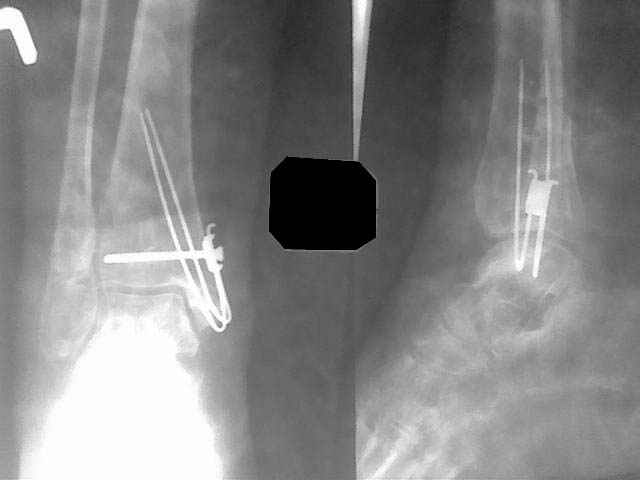

Re: Ложный сустав медиальной лодыжки

В данном случае - ложный сустав внутренней лодыжки на фоне оперативного лечения кортикальным винтом 3,5 и спицей. Часть внутренной лодыжки была лизирована. Проведена костная аутопластика. Результат налицо.